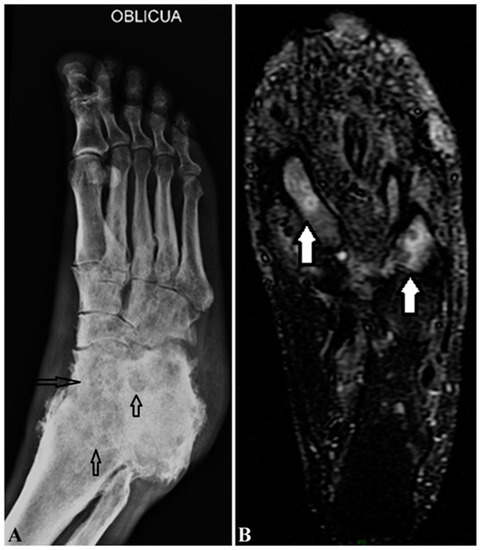

| Radiograph | Normal density and structure of the bone if not involved, “punched out” sign on the bone if involved [29] | “punched out” sign on the bones if involved (Figure 4A) [29] |

| Magnetic Resonance Imaging (MRI) and ultrasonography | “Dot in Circle” [12,29,30] Discrete small round hyperintense circles with central hypointense dots in the hypointense matrix of mass | “Dot in Circle” [29,30] Multiple small round hyperintense circles with central hypointense dots in the hypointense matrix of mass (Figure 4B) |